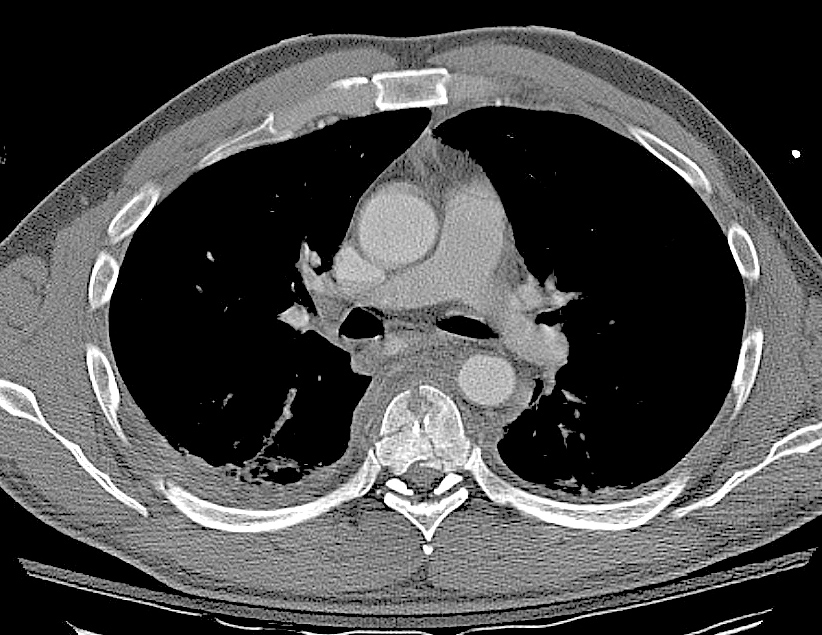

Gallery Blunt Chest Trauma Spine trauma Case 4c

Case 4c